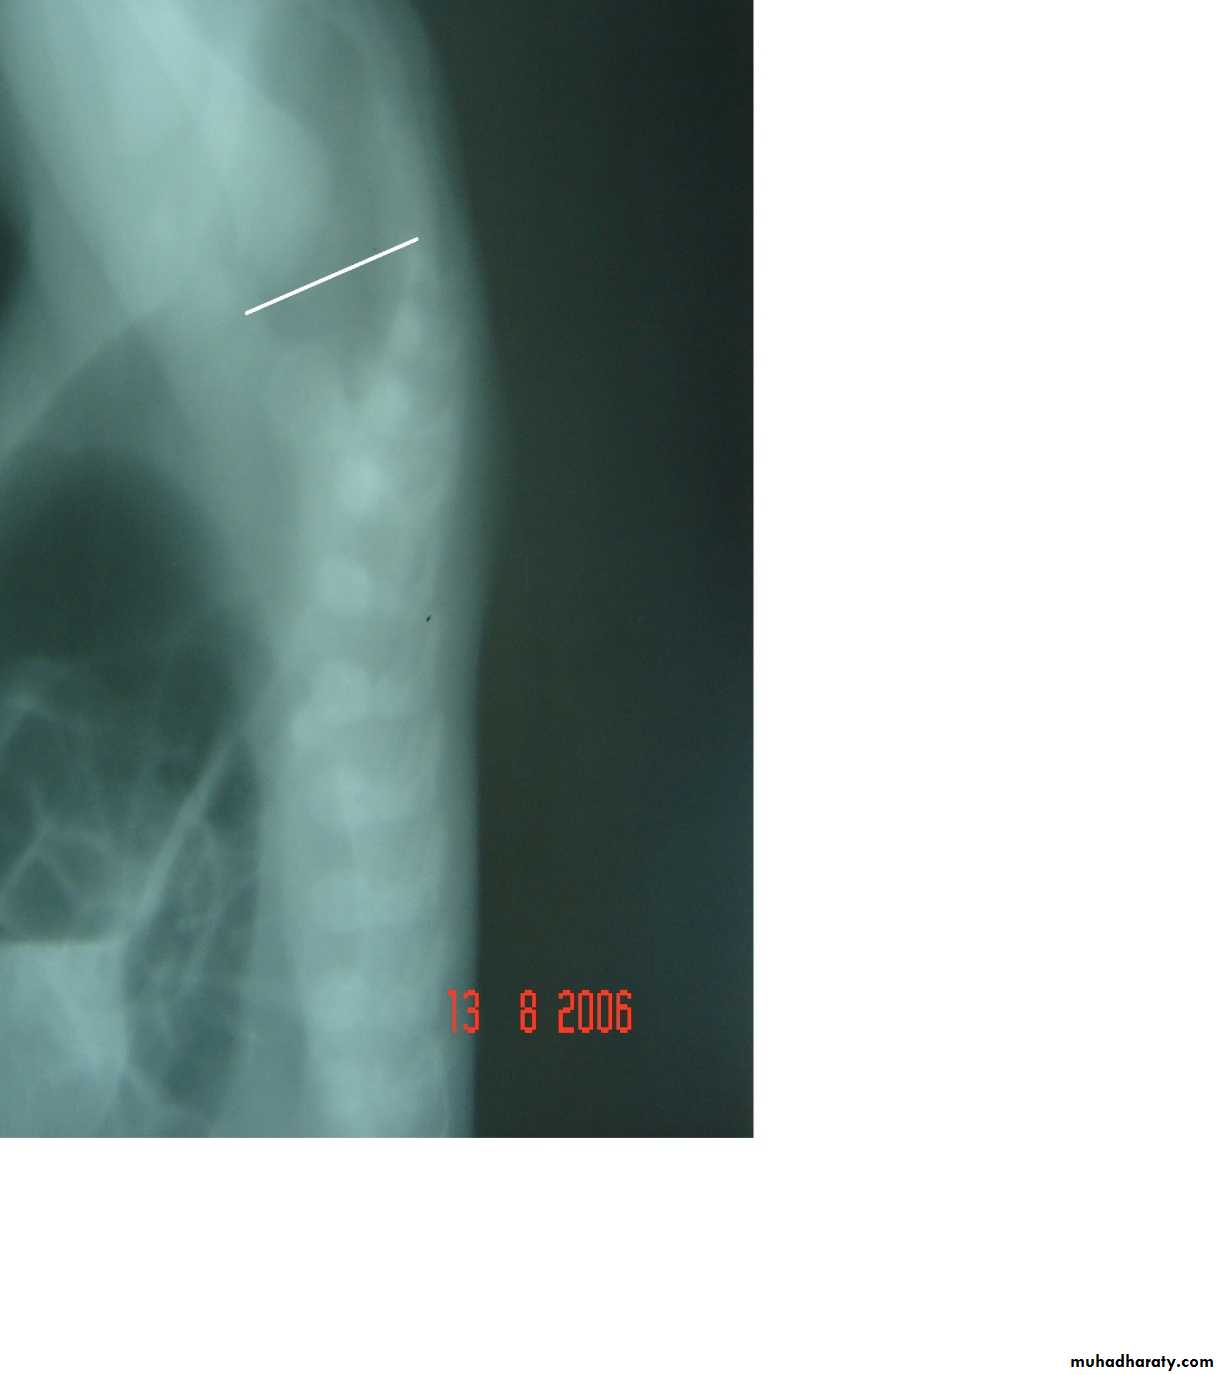

Respiratory Distress in the Newborn

Scaphoid abdomen